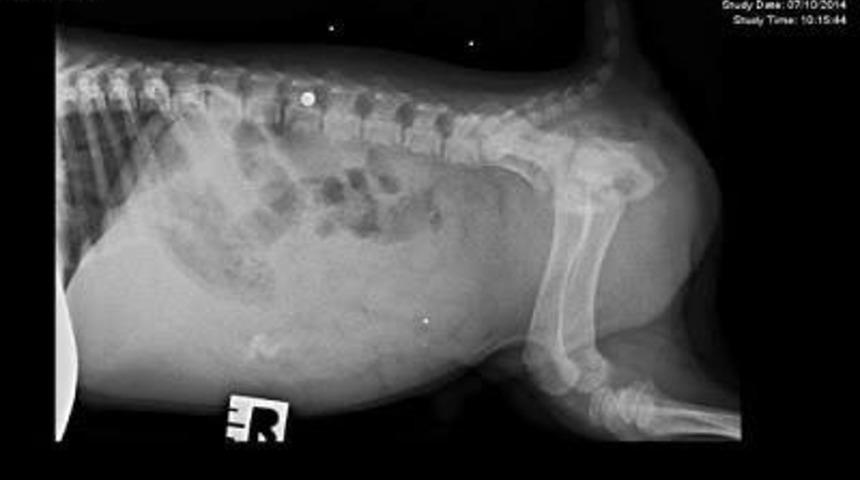

Oakley bir kaç aylıkken omurgasından kurşun yedi...

Zaten bu sebeple adı Bulletproof yani Kurşungeçirmez Oakley. Küçük köpeğin kurşunu nasıl yediği bilinmiyor. Tek bilinen gizemli birinin hayvanı barınağa terk ettiği. O zamandan beri köpekçik yürüyemiyormuş.